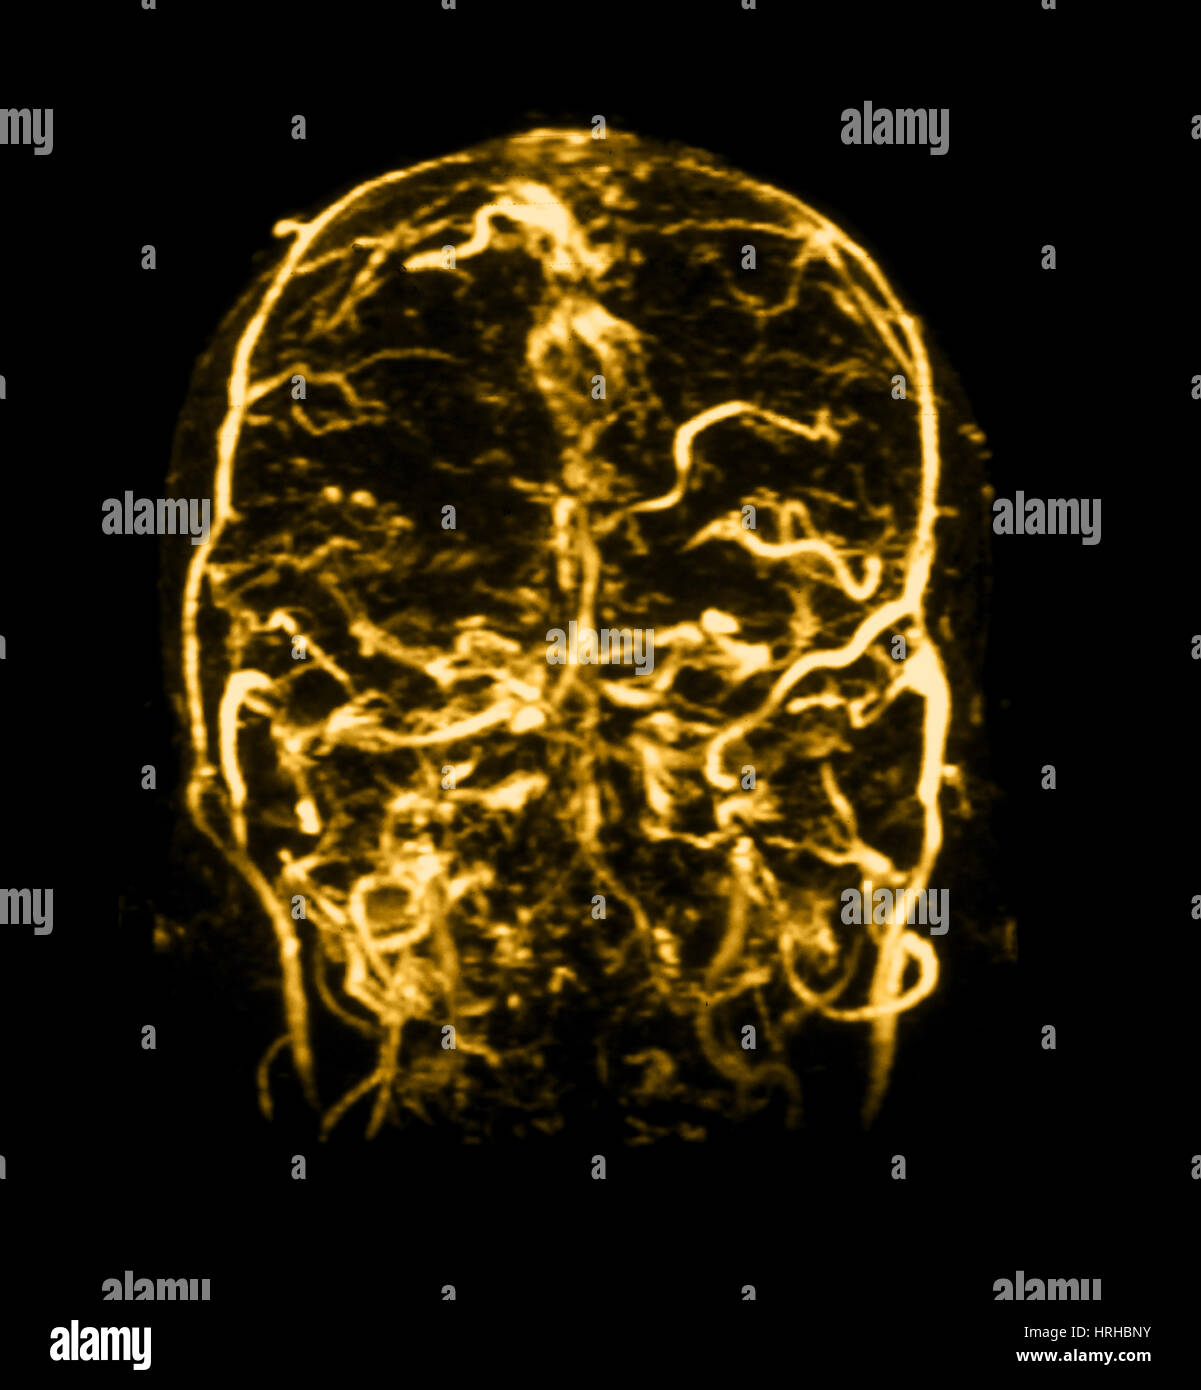

Cerebral venous anatomy on resonance venogram (MRV What Is A Mri Venogram A diagnostic procedure that uses a combination of a large magnet, radiofrequencies, and a computer to produce detailed images of organs and. After the dye is in your veins, your doctor will use a type. Providers use this test to diagnose deep. A venogram is a test done by injecting contrast dye into your veins. Magnetic resonance (mr) venography is. What Is A Mri Venogram.

Intracranial Resonance Venogram Photograph by Medical Body What Is A Mri Venogram It may or may not require the injection of a contrast. After the dye is in your veins, your doctor will use a type. Mrv stands for magnetic resonance venography. Providers use this test to diagnose deep. A venogram is a test done by injecting contrast dye into your veins. A diagnostic procedure that uses a combination of a large. What Is A Mri Venogram.